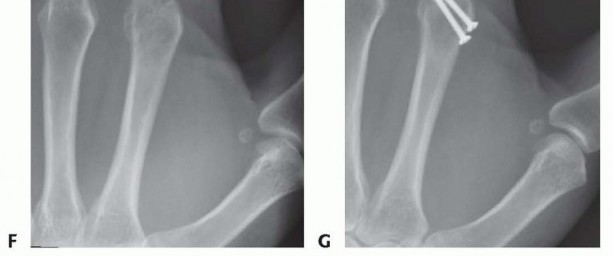

TECH FIG 6 • (continued) F,G. Intra-articular head fracture stabilized with extra-articular screws.